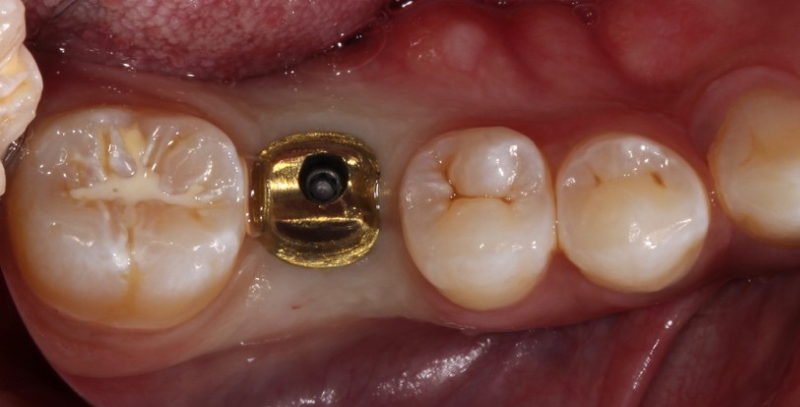

The “screwmentable” implant crown is another possible treatment option that combines the advantages of cement-retained and screw-retained implant restorations. In this crown, the abutment and implant crown are cemented extraorally. This can be done by the lab before the appointment or chairside.

In the chairside procedure, the abutment is placed on the implant, and the implant crown is adjusted as if it were a cement-retained restoration. After the contacts and occlusion are adjusted, the abutment is removed, the implant crown is cemented to the abutment extraorally, and excess cement is removed.

The abutment-crown complex now acts like a screw-retained restoration ready to be delivered.